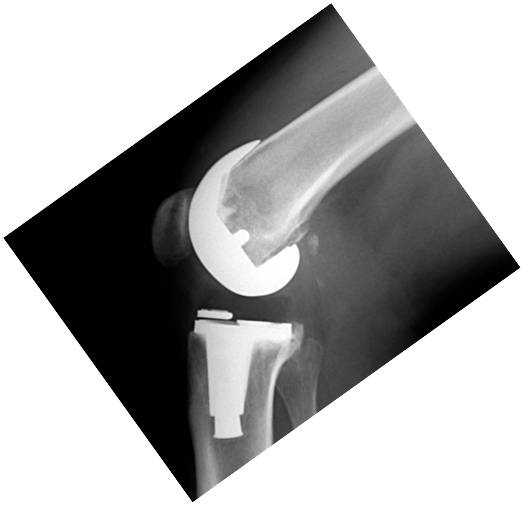

Rango de movilidad y resultados funcionales en tres diseños diferentes de artroplastia de rodilla primaria. Estudio Comparativo. [Range of motion and functional results in three different designs of total knee arthroplasty].